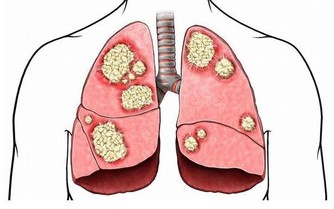

肝臟是維持人體健康的重要器官。

人們通過腸胃攝入的食物以及通過皮膚吸收的物質都需要經過肝臟的處理,因而肝臟經常和許多有害物質接觸。肝功能受到損傷的表現有:過敏、營養不良、高膽固醇、高甘油三酯和膽結石等。